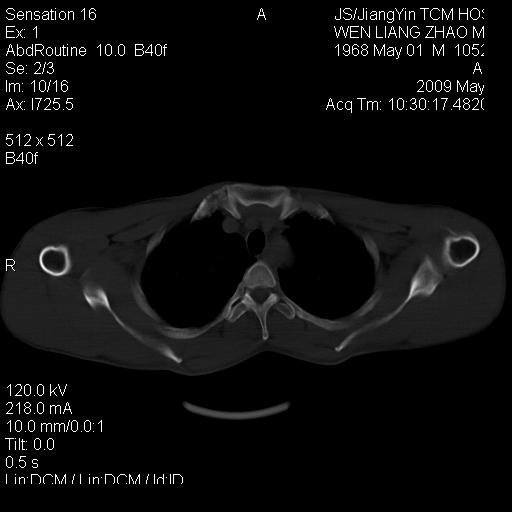

标题: CT19762:左侧喙突处压痛二年。考虑骨样骨瘤。 [打印本页]

标题: CT19762:左侧喙突处压痛二年。考虑骨样骨瘤。

左侧喙突处压痛二年。考虑骨样骨瘤。

病灶外缘膨胀明显,灶缘硬化较少,结合病史较符合骨母细胞瘤,其他亦不排除如软骨及软骨母细胞瘤等(病灶形态,成份较符合,发病部位也符合,只是年龄较大),骨样骨瘤多有较明显的自发性痛,且夜间痛明显,病史为压痛两年,不太符合.

多考虑内生性软骨瘤。年龄及发病部位及病史不支持骨样骨瘤。

支持骨样骨瘤(瘤巢小于1.5mm),骨母细胞瘤又称为巨大骨样骨瘤指瘤巢大于2cm的骨样骨瘤.

首先考虑内生软骨瘤,其次才考虑骨样骨瘤。